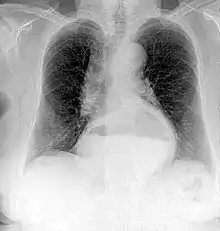

A chest radiograph of a female patient, demonstrating a hiatal hernia

Since Röntgen's discovery that X-rays can identify bone structures, X-rays have been used for medical imaging.[98] The first medical use was less than a month after his paper on the subject.[34] Up to 2010, five billion medical imaging examinations had been conducted worldwide.[99] Radiation exposure from medical imaging in 2006 made up about 50% of total ionizing radiation exposure in the United States.[100]

Projectional radiography is the practice of producing two-dimensional images using X-ray radiation. Bones contain a high concentration of calcium, which, due to its relatively high atomic number, absorbs X-rays efficiently. This reduces the amount of X-rays reaching the detector in the shadow of the bones, making them clearly visible on the radiograph. The lungs and trapped gas also show up clearly because of lower absorption compared to tissue, while differences between tissue types are harder to see.

Projectional radiographs are useful in the detection of pathology of the skeletal system as well as for detecting some disease processes in soft tissue. Some notable examples are the very common chest X-ray, which can be used to identify lung diseases such as pneumonia, lung cancer, or pulmonary edema, and the abdominal X-ray, which can detect bowel (or intestinal) obstruction, free air (from visceral perforations), and free fluid (in ascites). X-rays may also be used to detect pathology such as gallstones (which are rarely radiopaque) or kidney stones which are often (but not always) visible. Traditional plain X-rays are less useful in the imaging of soft tissues such as the brain or muscle. One area where projectional radiographs are used extensively is in evaluating how an orthopedic implant, such as a knee, hip or shoulder replacement, is situated in the body with respect to the surrounding bone. This can be assessed in two dimensions from plain radiographs, or it can be assessed in three dimensions if a technique called '2D to 3D registration' is used. This technique purportedly negates projection errors associated with evaluating implant position from plain radiographs.[101]